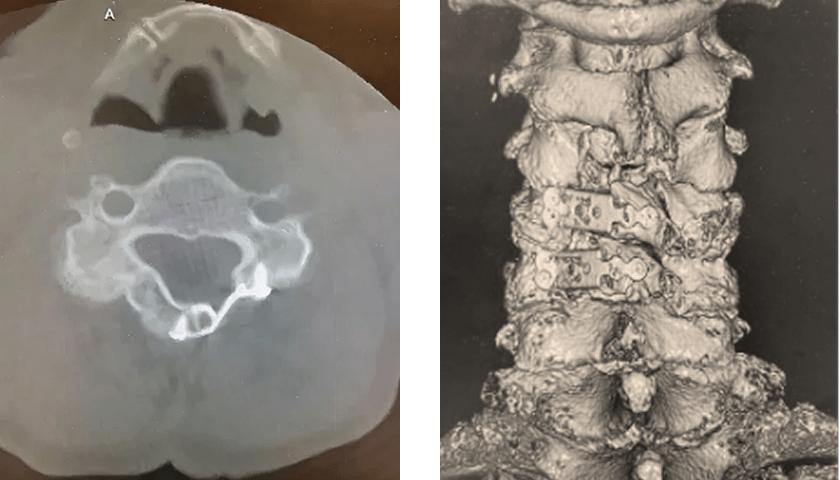

加齢に伴い、頚椎の椎間板が変性したり、骨棘(こつきょく)が形成されたり、靭帯が厚く硬くなることで、脊髄を通る空間(脊柱管)が狭くなり、脊髄が慢性的に圧迫される病気です。

頚椎椎弓形成術

後方から脊柱管を拡大し、脊髄の圧迫を取り除く

前方除圧固定術

突出した椎間板や骨棘を前方から除去して固定

いずれの方法も顕微鏡下手術を用い、安全で確実な手技を行っています。